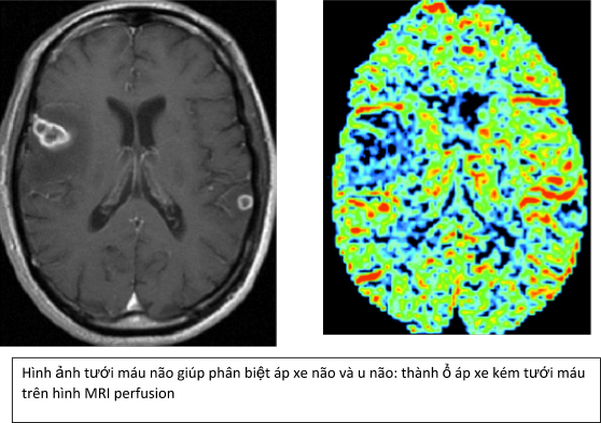

Trong U não MRI tưới máu não được sử dụng để chẩn đoán, đánh giá giai đoạn, tiên lượng và theo dõi đáp ứng với điều trị. Ví dụ như: đánh giá độ ác của u dựa vào thông số CBV, u độ ác tính cao có CBV cao, theo dõi sau điều trị: phân biệt giữa vùng Hoại tử do xạ trị giảm tưới máu và mô u thâm nhiễm tăng tưới máu...

3. Chỉ định/Chống chỉ định- Chỉ định: MRI tưới máu não được chỉ định trong nhiều bệnh lý hệ Thần kinh như đột quỵ não, u não, phân biệt U não với áp xe não, đánh giá sự co mạch dẫn đến thiếu máu não của xuất huyết dưới nhện, trong bệnh cảnh Chấn thương để đánh giá phù độc tế bào và Phù mạch do chấn thương, thay đổi tưới máu não do máu tụ và để tiên lượng.